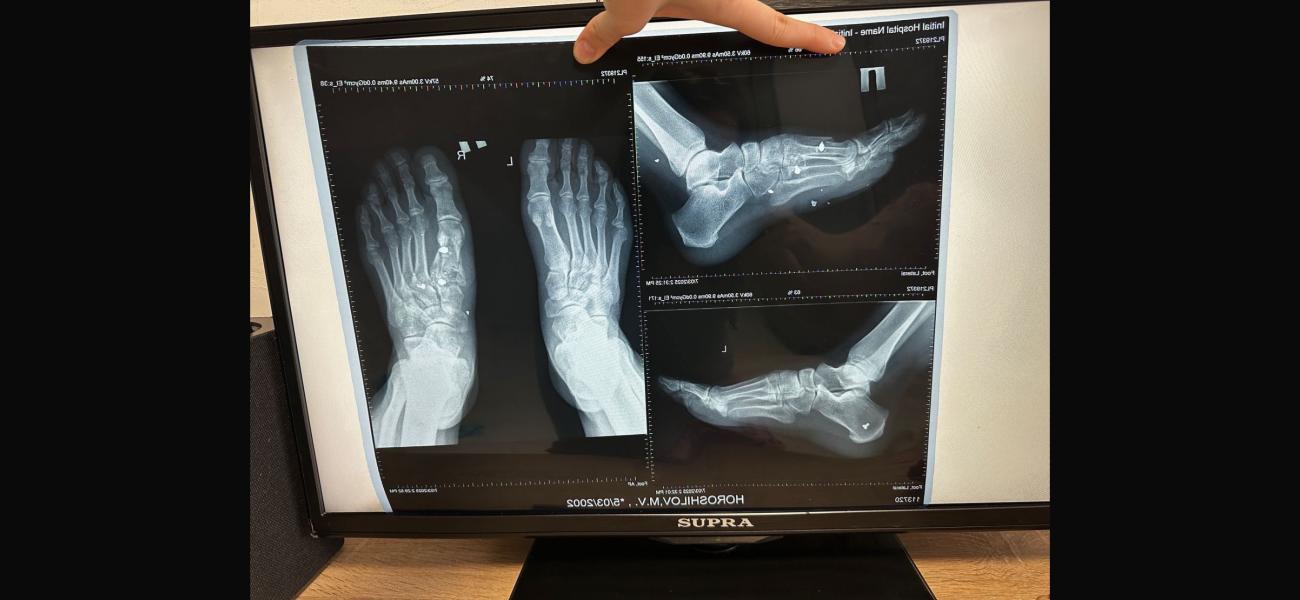

Ситуация следующая. Муж получил осколочное ранение, перелом плюсневой кости, осколок находиться в переломе прямо. Муж не чувствует 4х пальцев и не может шевелить ими. Хотя ранение было еще 22 января. К чему я, в госпитале усираются, что все само срастется и функционировать будет когда заживет, поэтому вынимать ничего не будут. Но как может срастись перелом, в котором осколок? В отпуске по ранению пытался лечь в госпиталь у нас в городе, до самого конца отпуска мурыжили что положат, ждите травматолога ( он бывает раз в сколько то дней, потому что по нескольким госпиталям бегает) когда мы наконец то 28го февраля попали к нему, он отказал в лечении. Сказал при части лечиться. Так вот хотелось бы услышать мнение врача. На случай если нам опять начнут говорить что все само пройдет.

П.с рентгены свои сделали, травматолога в частной не было в этот день, но сегодня сходим видимо просто в другую клинику, чтоб было на руках заключение. Но одно мнение специалиста хорошо, а два еще лучше

Если пальцы не шевелятся, возможно там ещё что-то мешает кроме осколка, может какое-то еще повреждение, проверьте по узи сухожилия